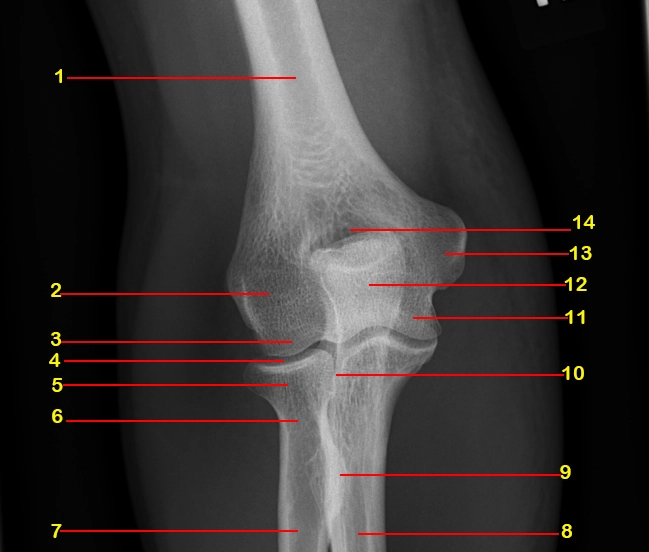

X Quang khớp khủy

16/03/2026